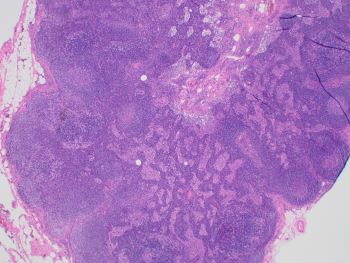

The lymph node shows extensive dermatopathic and other reactive changes with partial involvement by classic Hodgkin lymphoma (CHL), confirmed by immunohistochemical studies.

Images 1 and 2 show an enlarged lymph node with mostly intact architecture and marked paracortical expansion with pale staining areas. The expansion is mostly nodular. Although, areas of diffuse paracortical expansion are seen, such as on the left side of image 2. Images 3 and 4 show pale staining areas at high power magnification from different parts of the lymph node. Image 3 shows Langerhans and interdigitating dendritic cells with mostly small lymphocytes in the background. Image 4 shows Reed Sternberg cells with a mixed background of histiocytes, small lymphocytes, eosinophils, and plasma cells.